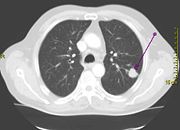

Lung cancer may be seen on chest x-ray and computed tomography (CT scan). The diagnosis is confirmed with a biopsy. This is usually performed via bronchoscopy or CT-guided biopsy. Treatment and prognosis depend upon the histological type of cancer, the stage (degree of spread), and the patient's performance status. Possible treatments include surgery, chemotherapy, and radiotherapy. With treatment, the five-year survival rate is 14%.

Performing a chest x-ray is the first step if a patient reports symptoms that may be suggestive of lung cancer. This may reveal an obvious mass, widening of the mediastinum (suggestive of spread to lymph nodes there), atelectasis (collapse), consolidation (pneumonia), or pleural effusion. If there are no x-ray findings but the suspicion is high (such as a heavy smoker with blood-stained sputum), bronchoscopy and/or a CT scan may provide the necessary information. Bronchoscopy or CT-guided biopsy is often used to identify the tumor type.

Screening refers to the use of medical tests to detect disease in asymptomatic people. Possible screening tests for lung cancer include chest x-ray or computed tomography (CT) of the chest. So far, screening programs for lung cancer have not demonstrated any clear benefit. Randomized controlled trials are underway in this area to see if decreased long-term mortality can be directly observed from CT screening.

If investigations confirm lung cancer, CT scan and often positron emission tomography (PET) are used to determine whether the disease is localised and amenable to surgery or whether it has spread to the point where it cannot be cured surgically.